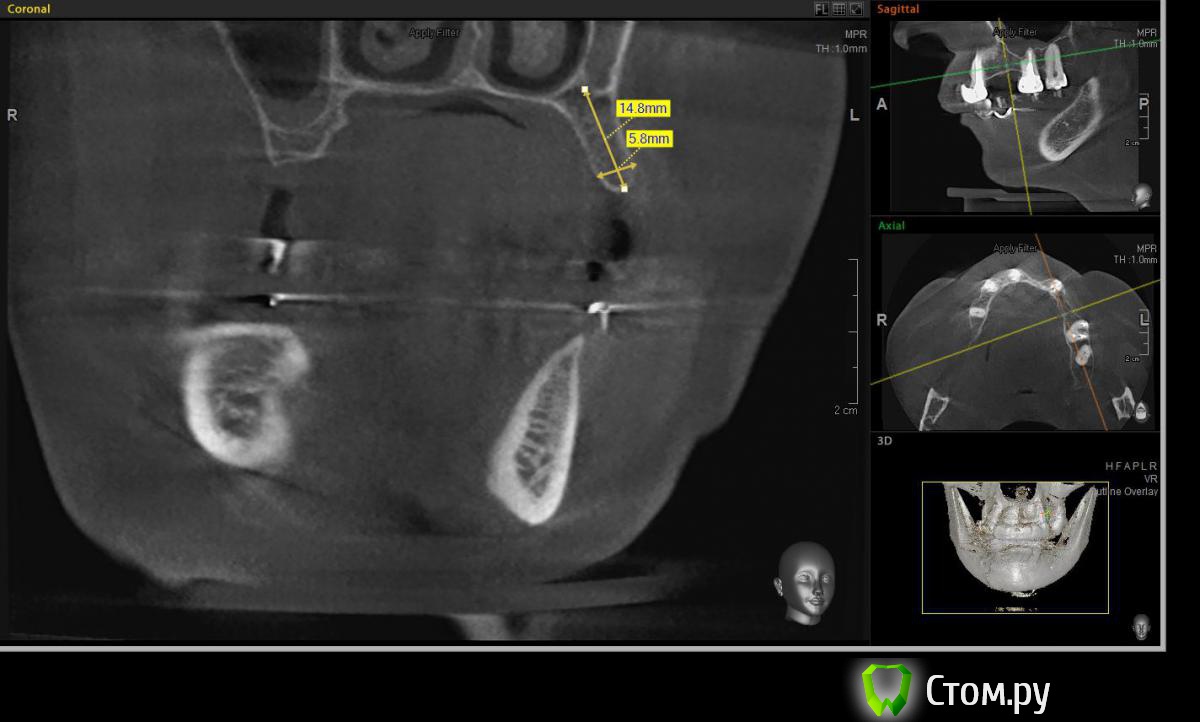

Евгений Ходыкин Опубликовано 22 июля, 2014 Автор Поделиться Опубликовано 22 июля, 2014 Дабы не плодить тем решил очередной случай выложить сюда Решили с пациенткой пока начать с в.ч. В планах имплантация в область отсутствующих 1.6, 1.4, 1.2, 2.1, 2.2, 2.4, 2.5. С 1.6 самому более менее все понятно, мануальных навыков хватит) Прошу помощи коллег относительно остальных областей. Фронт особливо печален... Забегая наперед скажу, что блоки еще не делал. Ауто точно пока брать не планирую, ибо нет даже теоретических навыков. Хочу начать все-таки с аллоблоков. У кого какие будут мнения, заранее спасибо) Ссылка на комментарий